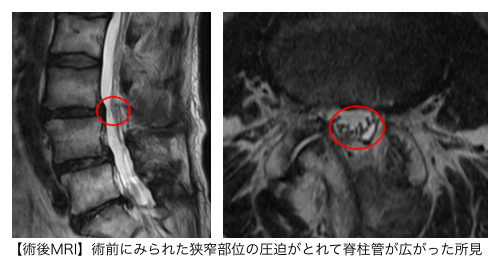

腰椎MRIからL3/4狭窄症が痛みの原因と判断し、PEL(脊柱管狭窄症内視鏡下手術)を行いました。同時に、神経修復の効果を期待して歯髄幹細胞上清液の投与も行いました。

手術の翌日には、術前に認められた腰痛と左殿部の痛み、痺れが軽減。術前の痛み・痺れを10とすると、手術後1ヶ月で0となりました。